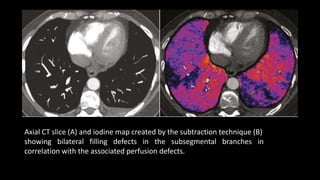

Axial CT slice (A) and iodine map created by the subtraction technique (B)

showing bilateral filling defects in the subsegmental branches in

correlation with the associated perfusion defects.